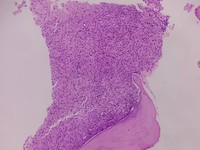

• GZL HE

Arun Ravi;Girish ...

B-cell lymphoma u...